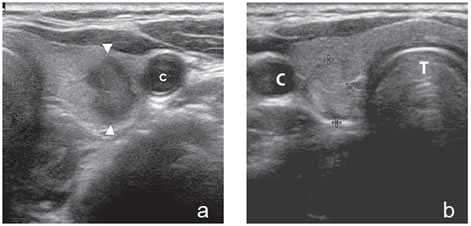

Un nódulo que tiene un componente quístico significativo, usualmente es un nódulo benigno hiperplástico, que ha acumulado abundante coloide (Figura 2a) o bien, un nódulo sólido que ha experimentado un proceso de degeneración colicuativa o hemorragia (Figura 2b). El coloide o el contenido líquido de un nódulo se ve anecogénico (negro en la imagen ecográfica) y las estructuras sólidas se ven ecogénicas (distintos tonos de grises), siendo la ecogenicidad similar al del parénquima tiroideo. En un nódulo sólido la ecoestructura y la ecogenicidad pueden ser variables. En general, la frecuencia de carcinoma es muy baja en nódulos quísticos13 y la mayoría de los carcinomas se presentan como nódulos sólidos (Figura 2c).

Figura 2. a) Quiste coloideo anecogénico y focos ecogénicos (flecha) con artefacto en cola de cometa; b) Nódulo mixto sólido-quístico (cabezas de flechas). Imagen vegetante (flecha) adherida a un tabique que se proyecta al lumen; c) Comparación entre el aspecto ecográfico de un cáncer papilar sólido (flecha abierta) y un quiste coloideo anecogénico.